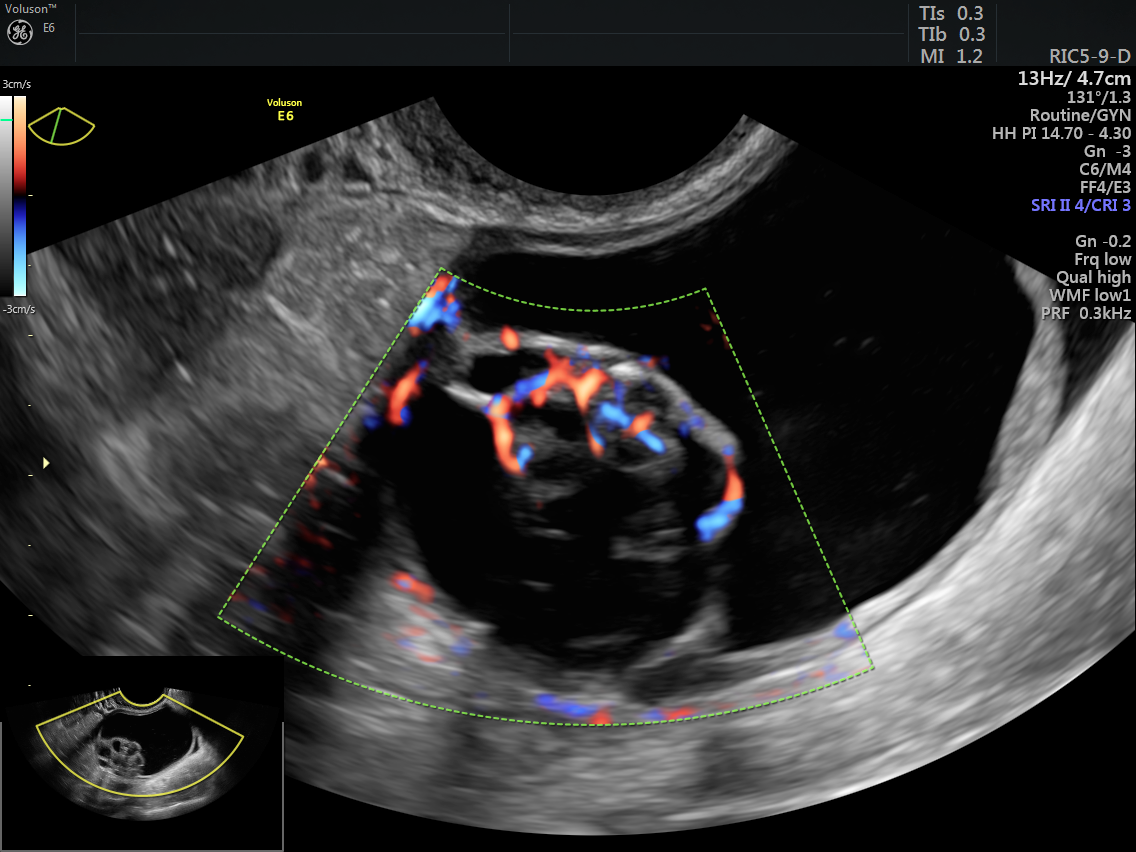

The IOTA Simple Rules model consists of 10 features, five of which are considered benign, or B-features, and five of which are considered typical for malignant tumors, or M-features. Besides accounting for the presence or absence of ascites and acoustic shadows, the size and number or papillary projections and other mass characteristics seen on ultrasound, this model also includes a color score. The absence of color Doppler flow is assigned a color score of 1, and is considered benign (B-feature). The color score increases with the amount of color flow seen, up to a color score of 4 (very strong blood flow), which can indicate a malignant or M-feature.

While 2D and 3D ultrasound alone are designed to visualize structures or tissues inside the body, the inclusion of color Doppler imaging can reveal important clinical clues by showing the presence or absence of blood flow, as well as the direction of blood flow. The International Journal of Oncology notes that many ovarian pathologies have clear distinguishing markers on ultrasound. For example, cyst contents will appear anechoic but will have no vascularization, while a teratoma, usually a benign mass, will have a mixed echogenicity because of its contents. A teratoma can also be vascularized if it is malignant.

Ovarian mass with color flow